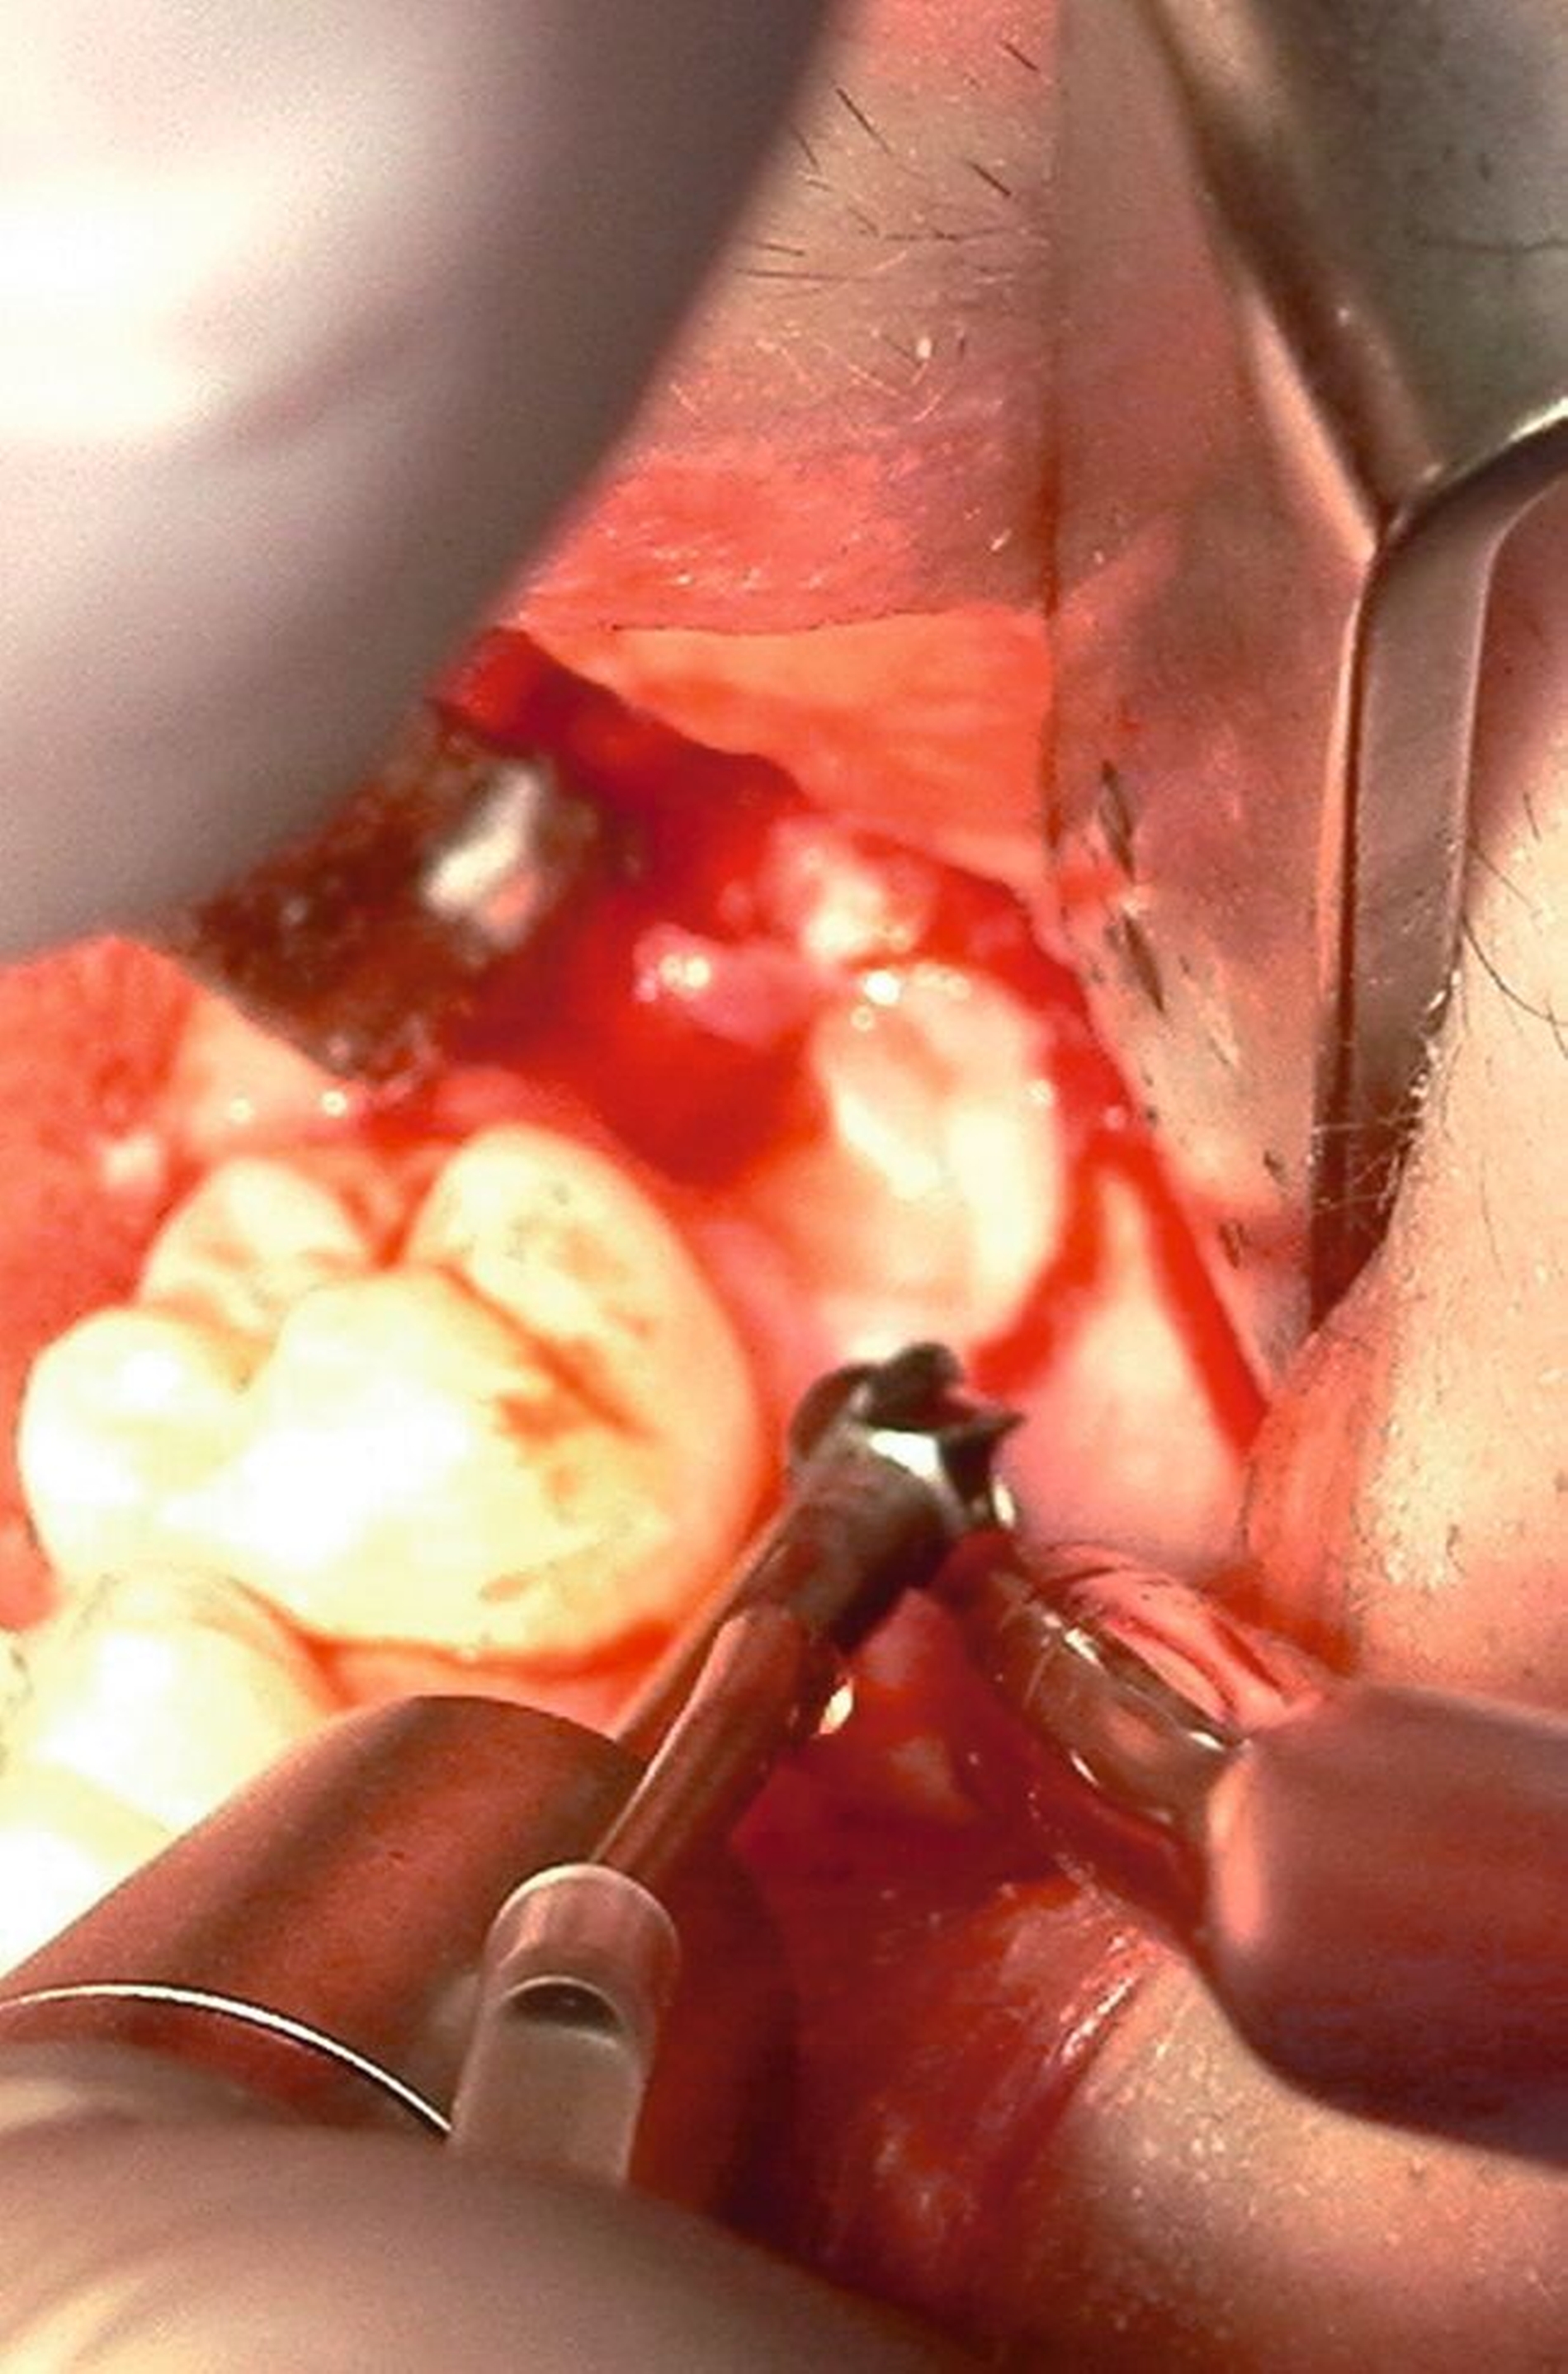

Nach Freilegung des Knochens kann ein Wundhaken nach Langenbeck eingesetzt werden sowie ein Bohr-Raspatorium zum Schutz des N. lingualis subperiostal lingual [Gutwald et al., 2019]. Unter Verwendung eines rotierenden Instruments (Kugel- und Lindemann-Fräse) oder Piezochirurgie wird der Knochen im Bereich der Zahnkrone abgetragen und diese freigelegt (Abbildung 8). Danach kann der Weisheitszahn vorsichtig mithilfe eines Bein‘schen Hebels anluxiert oder, falls dies noch nicht gelingt, mittels einer Lindemann-Fräse geteilt werden. Dabei wird am größten Kronendurchmesser die Krone mit der Fräse abgetrennt und die Wurzel anschließend separat entfernt (Abbildungen 9 und 10) [Gutwald et al., 2019; Schwenzer, 2019].

Anschließend erfolgt die sorgfältige Kürettage unter Schutz des am Boden der Extraktionsalveole liegenden Canalis mandibularis, die Entfernung von Granulationsgewebe sowie des Follikelepithels. Die Wurzelspitze sollte auf Vollständigkeit überprüft werden, um eine Wurzelfraktur auszuschließen (Abbildung 11).

Nach Darstellung des Knochens kann der Weisheitszahn meist schon mit dem Hebel anluxiert oder mittels rotierendem Instrument freigelegt werden. Dabei muss möglichst oberhalb des Zahnäquators angesetzt werden, sonst kann der Zahn in die Kieferhöhle oder in das umliegende Weichgewebe luxieren. Anschließend erfolgen die Kürettage, die Entfernung des Zahnsäckchens, der Knochenkanten und des Granulationsgewebes sowie die Prüfung einer Mund-Antrum-Verbindung (MAV) mittels Bowman-Sonde. Bei positiver Testung erfolgt die plastische Deckung mittels Mukoperiostlappen oder bei ausgedehnteren Defekten mittels Bichat-Fettpfropf (Abbildungen 14 und 15) [Gutwald et al., 2019; Schwenzer, 2019].